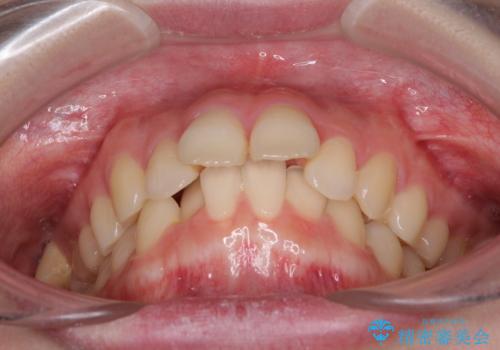

- 口元の突出感を気にして来院された患者様です。

左右ともに上顎奥歯が外を向き、下顎奥歯が内側に倒れているシザーズバイトであったため、補助装置により改善することとしました。

上下の咬み合わせは、下顎に対して上顎が相対的に前方にあったため、奥歯のシザーズバイト改善後に上顎左右第一小臼歯2本を抜歯し、上顎前突を改善していくこととしました。